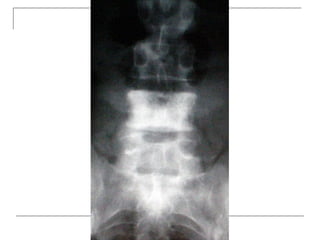

Plain radiograph

   AP

-loss of lumbar lordosis

-reduced disc space

-osteophytes

-deformity

-fracture (increase interpedicular distance)

-osteoporosis

-pedicle disruption

Plain radiograph  AP -loss of lumbar lordosis -reduced disc space -osteophytes -deformity -fracture (increase interpedicular distance) -osteoporosis -pedicle disruption